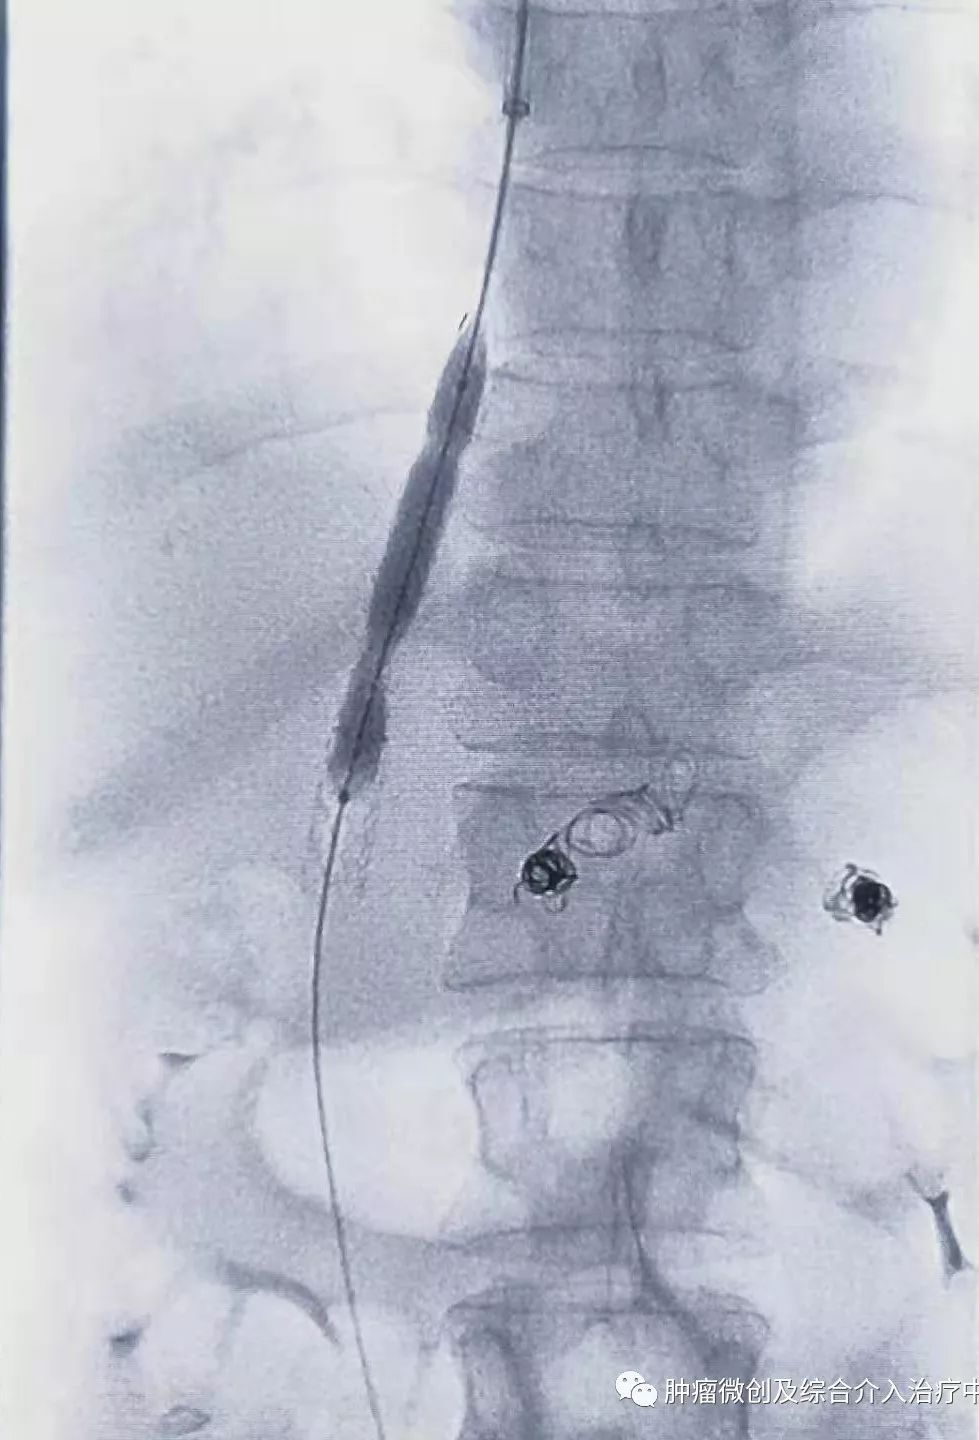

球囊扩张静脉-门脉支架:达到门脉-体静脉充分分流目的

再次造影可见:门脉血流流向-体静脉达到分流目的,术前侧压力42,术后25,门脉压力明显降低,达到防止再次出血目的。